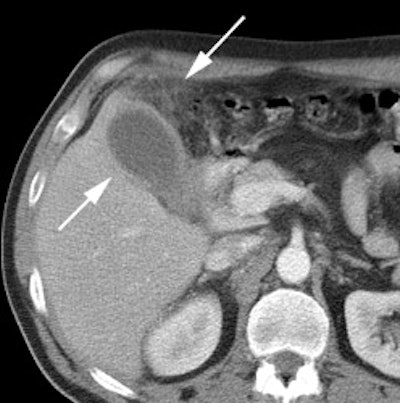

|

Benign adrenal lesion with FDG uptake: The patient shown below had a left adrenal mass which had remained stable for 2 years (white arrow). The stability over time and CT features would be consistent with a benign adrenal lesion- likely an adenoma. Note the marked FDG uptake within the mass on PET imaging (black arrows). Benign adrenal adenomas can accumulate FDG resulting in false positive exams. The use of PET/CT has been shown to improve the specificity of the PET exam. |